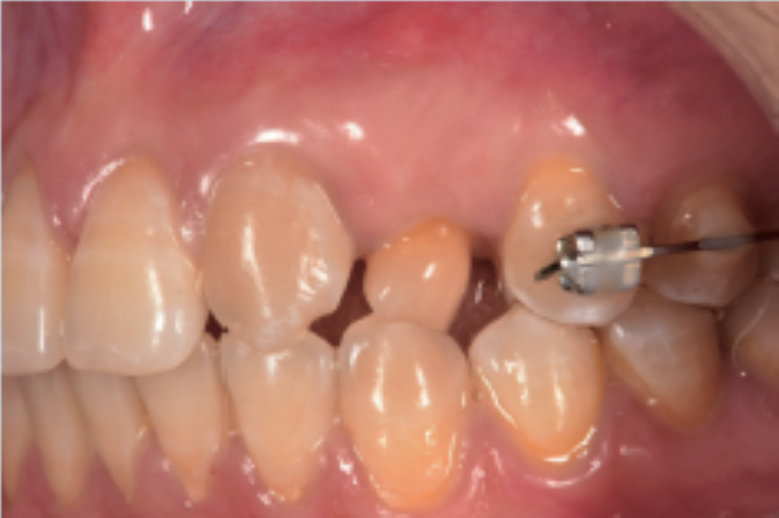

方法:患者轻咬合状态进行CBCT(NewTomTM,Verona,Italy)扫描,扫描结果以DICOM(digitalimagingandcommunicationinmedicine)格式导出。CBCT显示:左上乳尖牙牙根周围牙槽骨吸收,可用骨高度约15mm,颊舌径宽约6mm。

口内扫描利用3shape扫描制作伴有咬合面记录的数字化诊断印模。采用非接触式光学口内印模技术,对邻牙及正畸配件无损伤。将CBCT数据以DICOM格式导入3shape软件,进行颌骨三维重建,根据颌骨的三维解剖结构和咬合关系,设计种植的位置、角度、数目及深度,在此设计方案上利用3shape软件设计种植导板及个性化基台和临时牙。